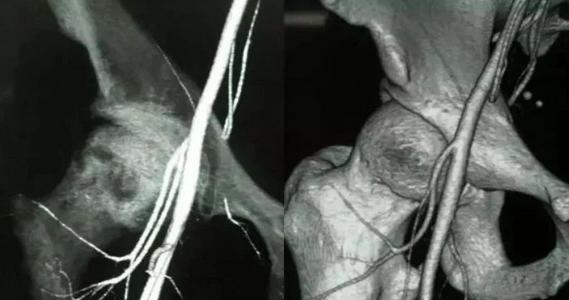

股骨头只有三根主要的血管动脉供应,如果三大供血动脉栓塞,就会导致供血不够,骨细胞就会慢慢“饿”死(此时,患者就会感到剧烈疼痛),从而引起骨细胞或股骨头缺血性坏死,因此股骨头坏死的治疗关键在于堵塞的这三大动脉血管。

⒈ 旋股外侧动脉:

发自股深动脉根部的外侧壁,在缝匠肌与股直肌深面行向外侧,分为升、降两支。

⒉ 选股内侧动脉:

旋股内侧动脉起于股深动脉根部的内侧壁,行向后内,在耻骨肌与髂腰肌之间进入深部,绕行股骨颈内侧至颈内侧到达臀部,是股骨头最主要的供血源。

⒊ 股骨头韧带动脉:

从髋内动脉发出的闭孔动脉的分支股骨头圆韧带动脉,提供股骨头凹部的血液循环,股骨干动脉升肢的发源地。